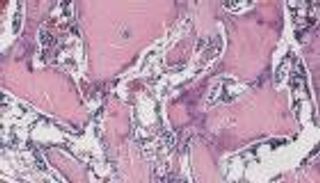

وأزال الباحثون الجين من الفئران البالغة، ليُلاحظوا أن الحذف أدى إلى فقدان سريع للخلايا الجذعية سريعة التدوير، التي تغذّي بطانة الأمعاء، كما وجدوا نصف الخلايا الجذعية الموجودة في منطقتيْن من الدماغ قد ضاعت، ما تسبّب في عجز بالتعلّم والذاكرة، وزيادة القلق ونقص حاسة الشم.

وقالت تيريزا وود الأستاذة المشاركة في جامعة "روتجرز نيو جيرسي": "عندما يتم إزالة الجين بشدّة، لا يمكن للخلايا الجذعية، الموجودة في غدد السطح الداخلي للأمعاء الدقيقة، مواصلة الدورة الطبيعية لاستبدال الخلايا، الأمر الذي ينجرّ عنه فشل الأعضاء.